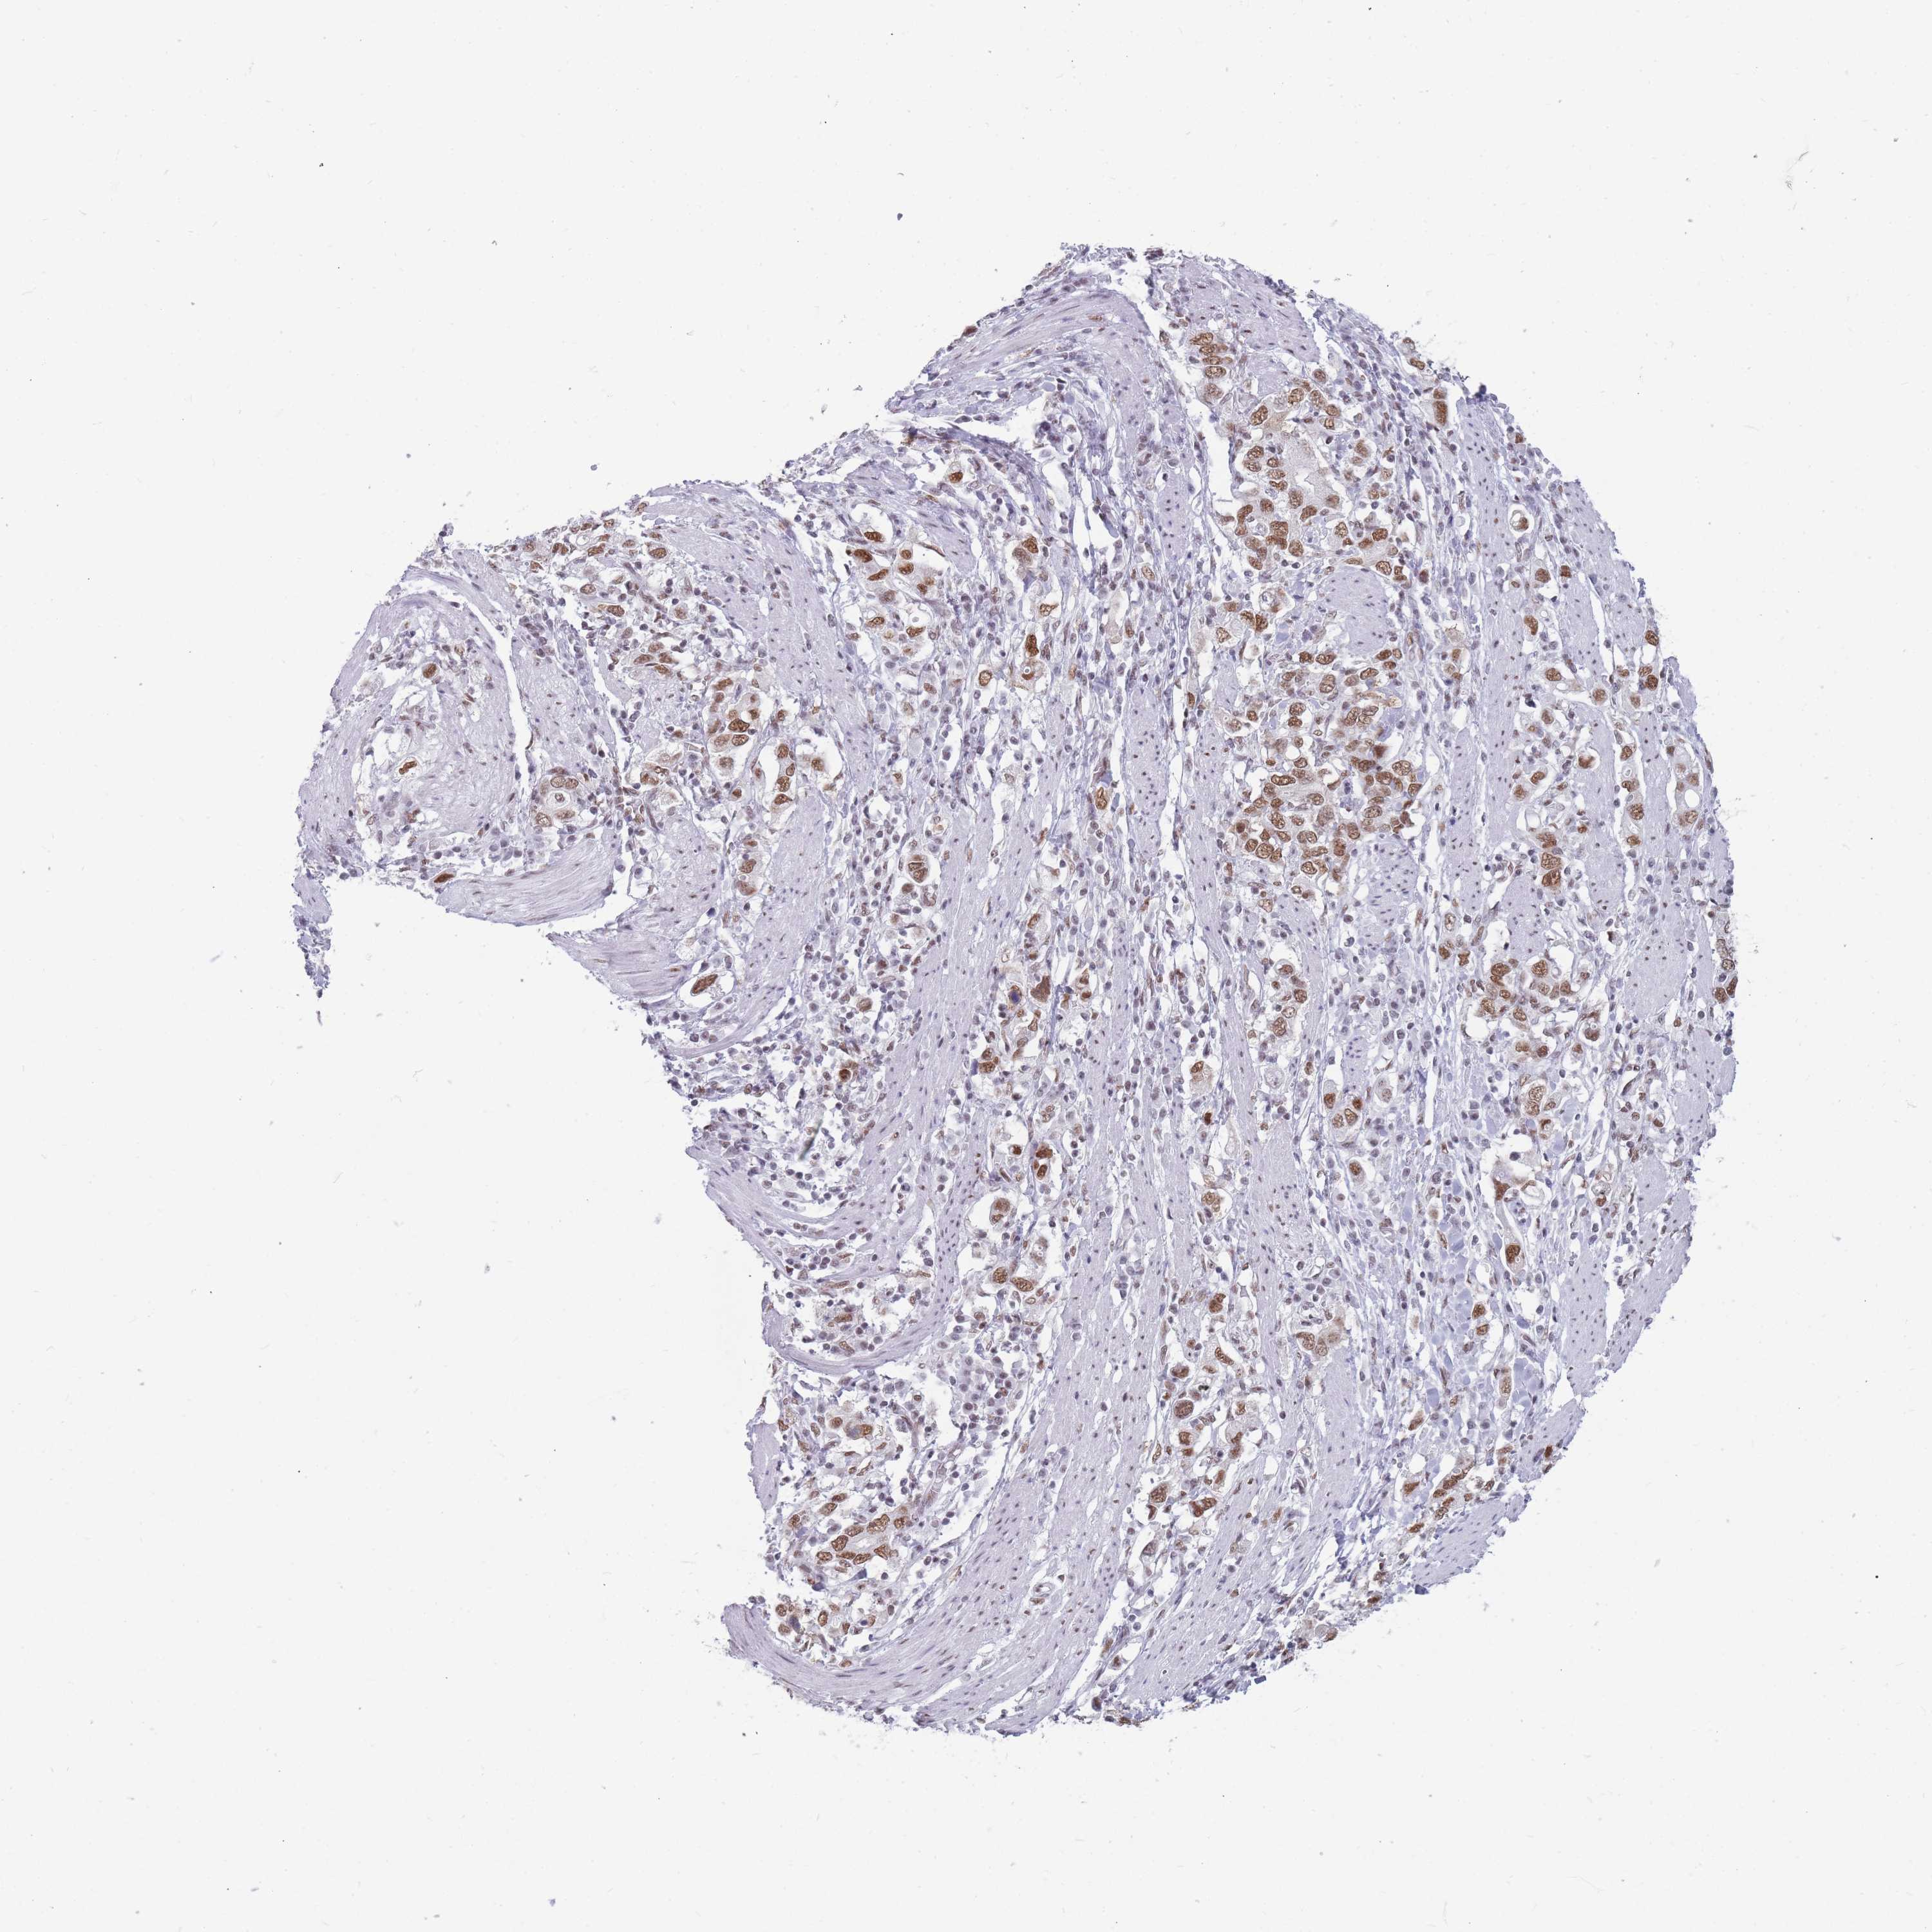

STOMACH CANCER - Protein expressioni

A mouse-over function shows sample information and annotation data. Click on an image to view it in a full screen mode. Samples can be filtered based on level of antibody staining by selecting one or several of the following categories: high, medium, low and not detected. The assay and annotation is described here.

Note that samples used for immunohistochemistry by the Human Protein Atlas do not correspond to samples in the TCGA dataset.

Antibody stainingi

Antibody staining in the annotated cell types in the current human tissue is reported as not detected, low, medium, or high, based on conventional immunohistochemistry profiling in selected tissues. This score is based on the combination of the staining intensity and fraction of stained cells.

Each image is clickable and will lead to virtual microscopy that enables deeper exploration of all samples and also displays staining intensity scores, fraction scores and subcellular localization as well as patient and tissue information for each sample.

Antibody HPA046290

Antibody HPA049475

Antibody CAB046477

Staining

High

Medium

Low

Not detected

Intensity

Strong

Moderate

Weak

Negative

Quantity

>75%

75%-25%

<25%

None

Location

Nuclear

Cytoplasmic/membranous

Cytoplasmic/membranous,nuclear

Adenocarcinoma, NOS